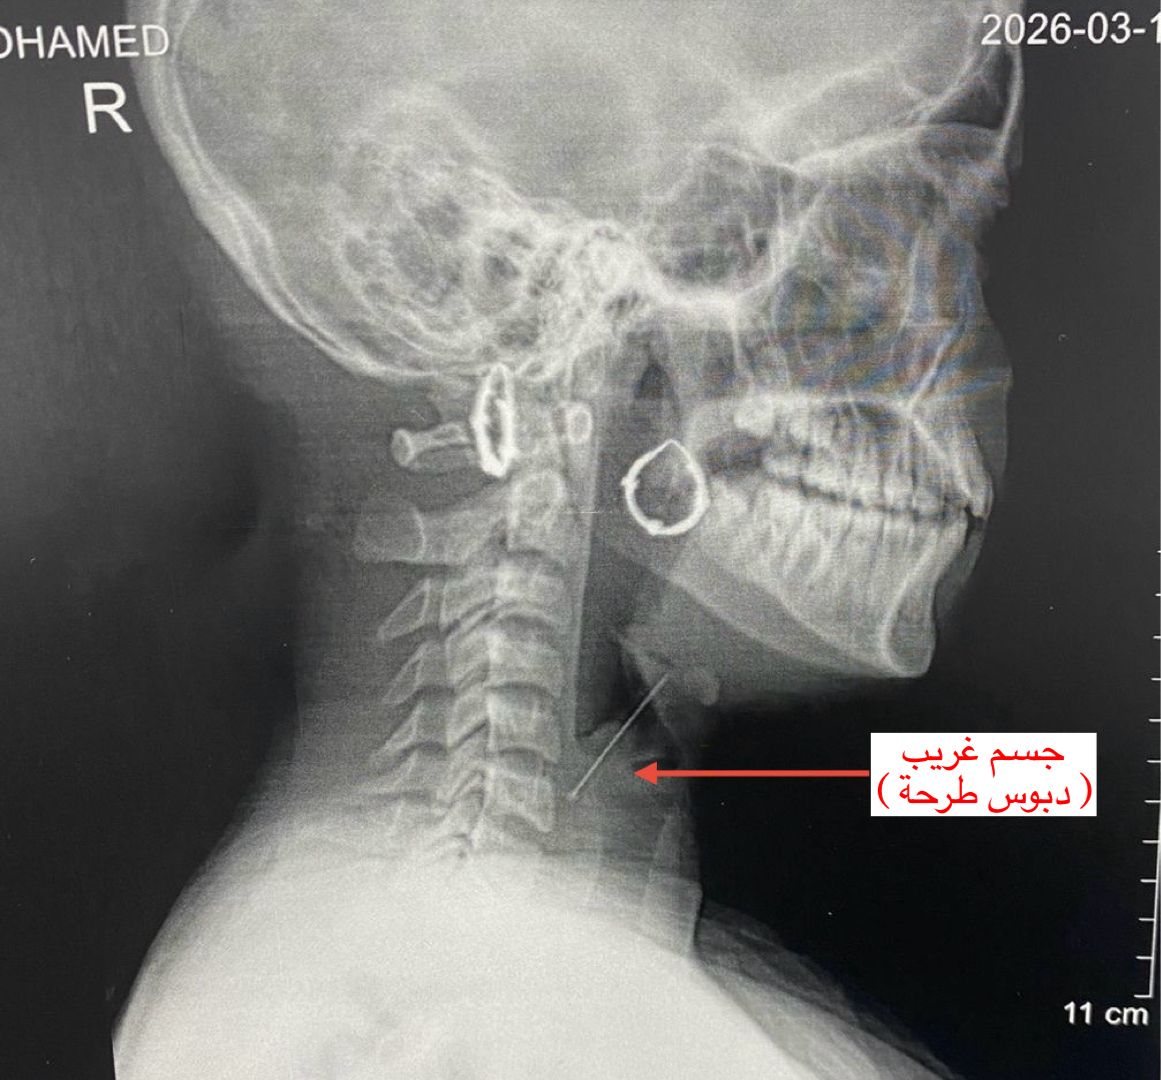

واستقبل قسم الاستقبال والطوارئ بالمستشفى المريضة وهي تعاني من آلام شديدة بالرقبة وصعوبة حادة في التنفس، حيث جرى على الفور إجراء الفحوصات والأشعة اللازمة التي كشفت عن استقرار الدبوس في منطقة دقيقة بمدخل مجرى التنفس، ما شكّل خطورة على حياتها.